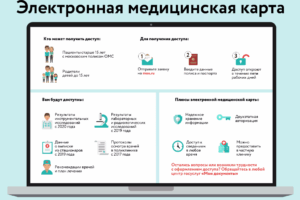

Электронные медкнижки: цифровизация откладывается ещё на год

Министерство здравоохранения России вновь пересмотрело сроки перехода на электронные медицинские книжки. Как стало известно из...